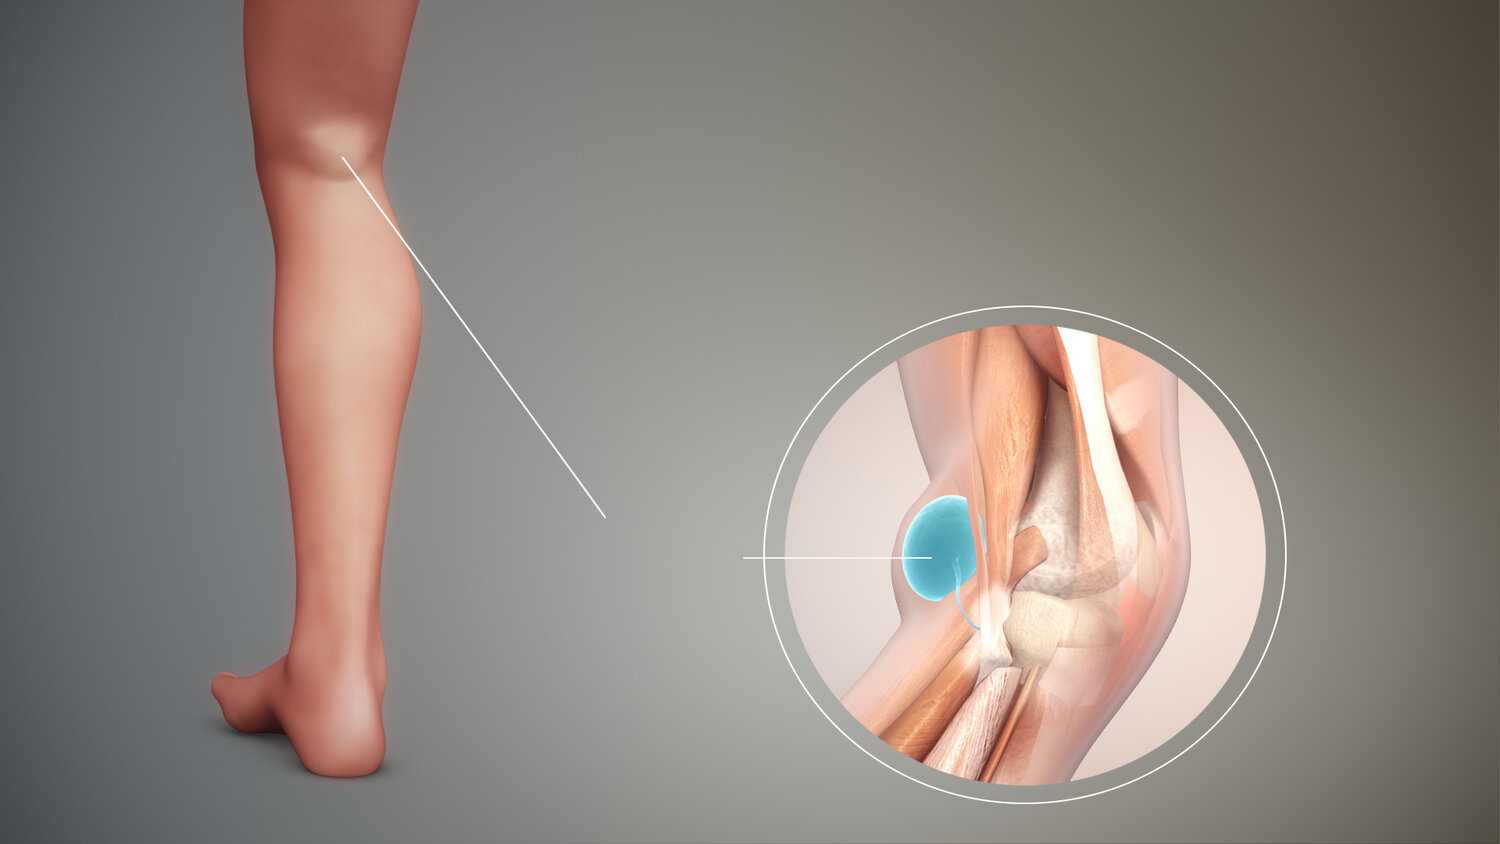

En Baker cyste er en væskefyldt hævelse bag knæet.

En Baker cyste opstår, når ledvæske ophobes bag knæet, ofte som følge af irritation eller skade i knæleddet. Cysten kan variere i størrelse og give ubehag ved bevægelse, men er i sig selv ufarlig. Hos nogle forsvinder den spontant, mens den hos andre kræver behandling, hvis den bliver for stor eller smertefuld.

En Bakers cyste er en væskefyldt hævelse, der udvikler sig bag knæet. Det er navngivet efter den britiske kirurg, der først beskrev tilstanden, Dr. William Baker.

En Bakers cyste opstår, når for meget væske akkumuleres i bursa, en lille sac, der findes i leddene. Dette kan ske af flere grunde.